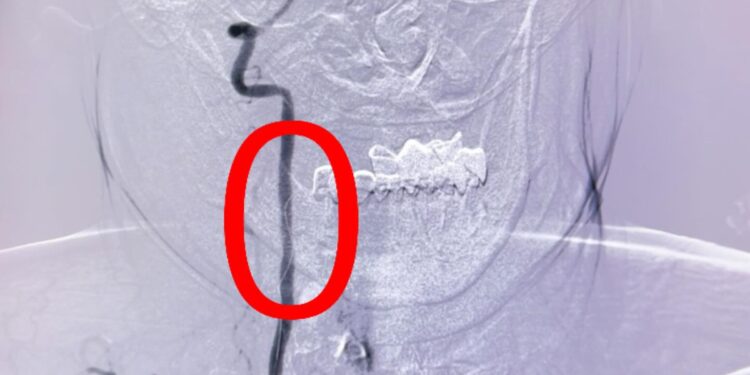

Сарыағаш аудандық орталық ауруханасының дәрігерлері ишемиялық инсульт диагнозы қойылған 55 жастағы науқасқа Омыртқа артериясын стенттеу отасын жасады. Өміріне қауіп төндіретін жағдай профилактикалық тексеру кезінде анықталған. Ота 1 сағатқа созылды.Ишемиялық инсульт — мидағы қан тамырының тромбпен немесе басқа бөгетпен бітеліп қалуы салдарынан болады. Бұл түрі инсульттің ең жиі кездесетін түрі — шамамен 80% жағдай.